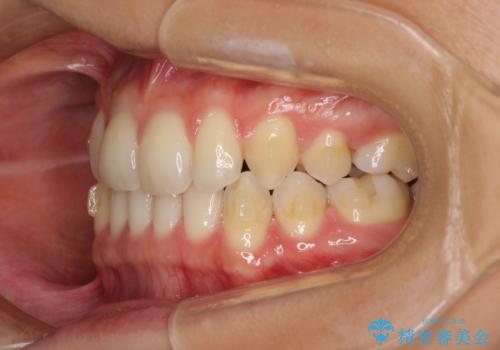

- 以前の矯正治療の後戻りにより、上の前歯にスペースができたことを気にして来院された患者様です。

インビザラインを用いて前歯のスペースを閉じつつ、上下の咬み合わせを構築していくこととしました。